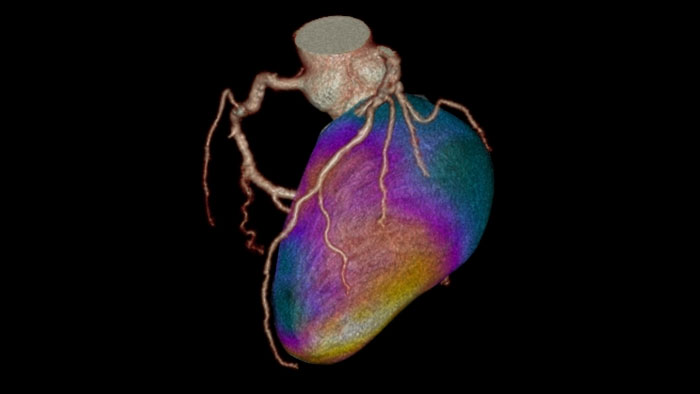

Dynamic color maps provide an assessment of myocardial risk

Provides automatic and manual tools to help visualize and assess signal intensity differences (in Hounsfield Unit) focusing on the left ventricular myocardium, providing quantitative myocardial perfusion measurements for CT images.